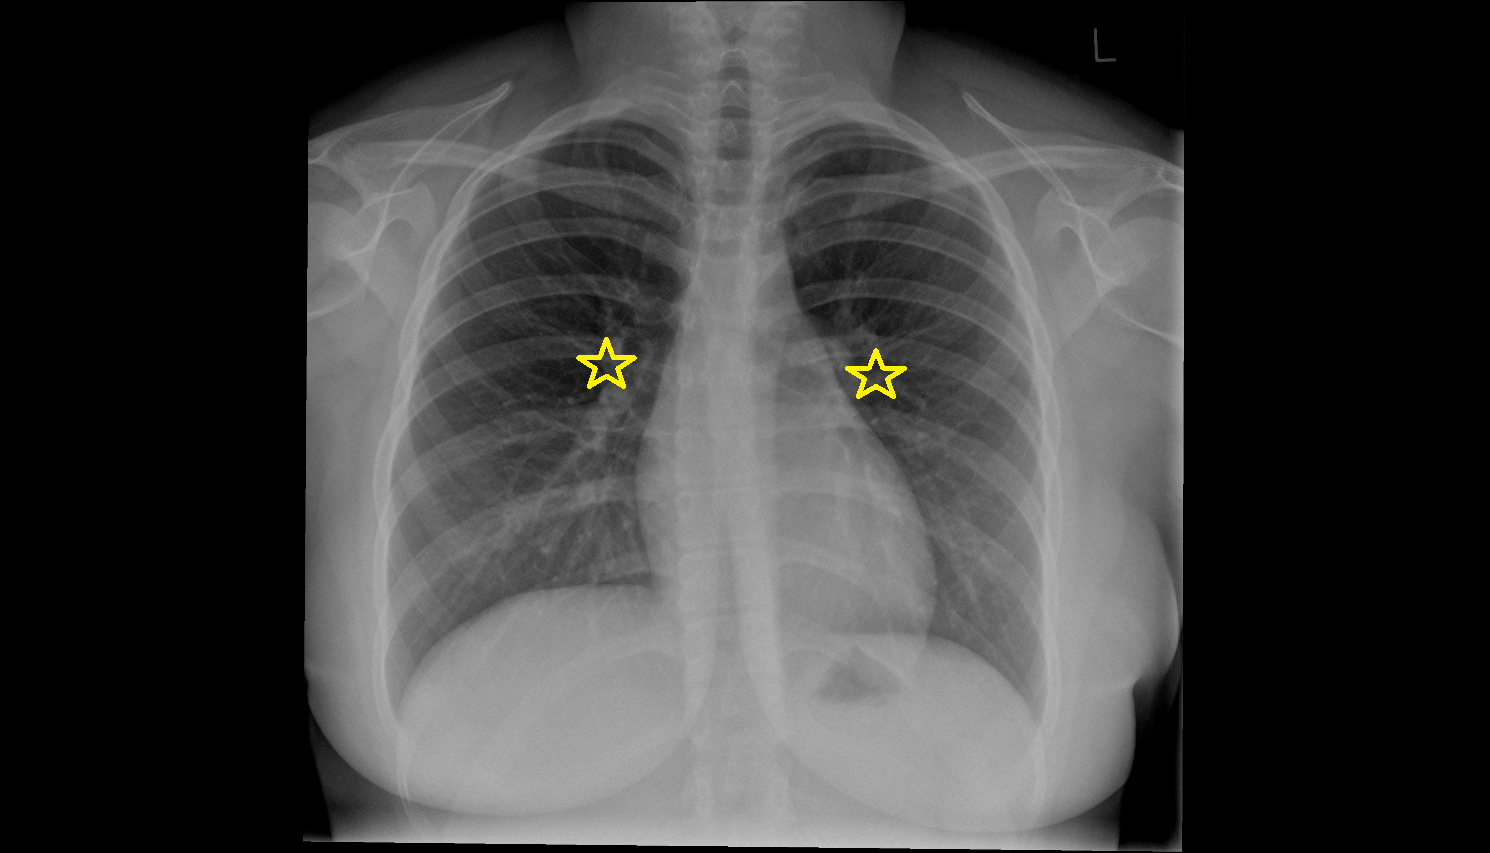

- Right lung (superior lobe)

- Right lung (middle lobe)

- Right lung (inferior lobe)

- Left Lung (Superior Lobe)

- Left lung (inferior lobe)